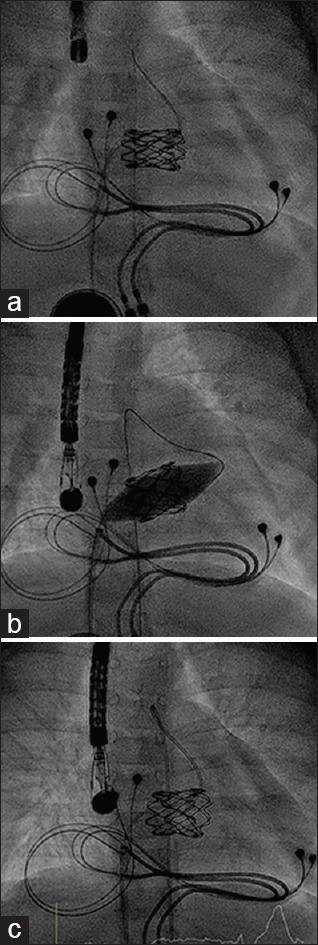

Infants requiring mitral valve replacement have few viable options. Recently, stented bovine jugular vein graft (Melody) has been surgically implanted in such cases. Herein, we report our experience, elaborating on evolution of implantation technique, pitfalls, as well as long-term outcome (including late dilatability).

Seven Melody valves were implanted (2013-2019). The median patient age and weight were 6.7 (1.8-30.5) months and 5.8 (4.6-9.5) kg, respectively. The indications for implantation were mitral stenosis and/or regurgitation postatrioventricular septal defect (AVSD) repair (5), congenital mitral valve dysplasia (1), and Shone's complex (1). Operative technique involved shortening the valve and creating a neo-sewing ring at 2/3 (atrial)-1/3 (ventricular) junction. Implantation was followed by intraoperative balloon dilatation.

Five out of seven patients survived the perioperative period (one death due to technical failure and the other due to acute respiratory distress syndrome postcardiopulmonary bypass). Two out of five medium-term survivors got transplanted (1) or died due to acute myeloid leukemia (1). No valves were replaced. The mean echo gradient at discharge was a median 4 (2-6) mmHg. None of the patients showed left ventricular outflow tract or pulmonary venous obstruction. Two Melody valves were dilated late (5 months and 3 years postoperatively), resulting in decreasing mean gradients from 6 to 1 and from 17 to 4 mmHg. At last follow-up, surviving Melody had a mean gradient of 4 (1-9) mmHg.

Mitral valve replacement with a Melody valve is feasible in infants, is reproducible, shows good immediate results, and offers the possibility of later dilatation. This technique offers a better solution compared to the existing alternatives for infants requiring a prosthetic mitral valve.